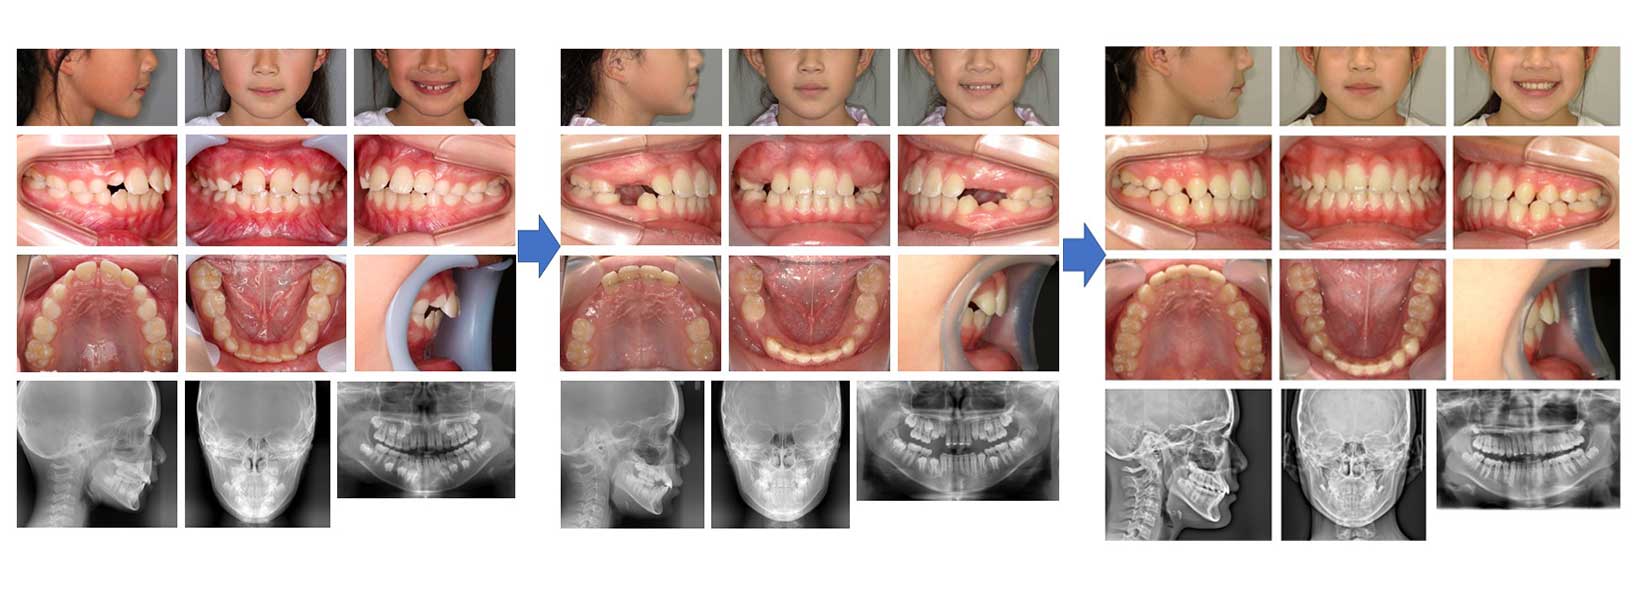

【治療例 K7386】初診時年齢:8歳8か月 / 性別:女性 / 主訴:歯並びがガタガタになりそう

症例の概要:この症例は、マウスピース型(アライナー型)矯正装置(インビザライン・ファースト™)を用いた症例である。上顎中切歯の正中離開及び唇側傾斜を気にされ来院された。現在第二期治療待ちである。

主訴:歯並びがガタガタになりそう

診断名:上顎中切歯の正中離開及び唇側傾斜

使用した主な装置:マウスピース型(アライナー型)矯正装置(インビザライン・ファースト™)

抜歯/非抜歯および抜歯部位:非抜歯

治療期間:1年6か月

治療回数:19回

アライナー枚数:初回28枚+追加①9枚 合計37枚使用